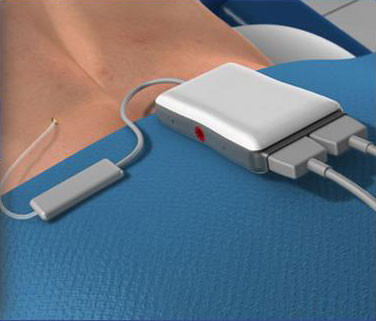

- Spinal Cord Stimulator Implant